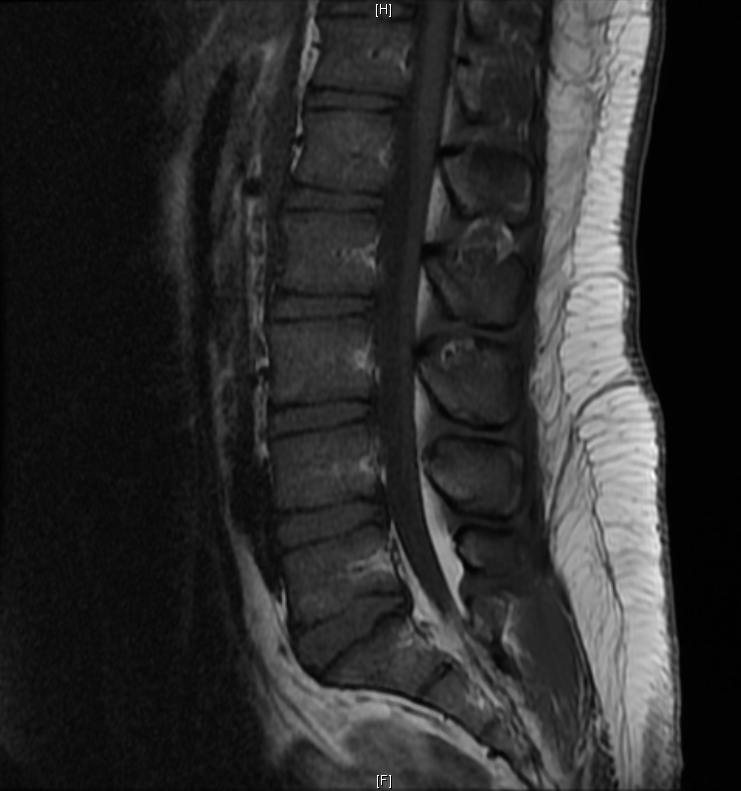

Case Presentation: A 26-year-old male without prior medical history was referred by a spine surgeon to the emergency department (ED) with weakness, numbness, and discoordination of the right leg, worsening over a four month period and resulting in multiple falls. He reported three weeks of urinary and bowel urgency and incontinence. He had a family history of multiple sclerosis (MS) in his aunt. Physical examination in ED revealed an obese patient with decreased sensation and strength in the right leg, tenderness over the thoracic spine, and absence of saddle anesthesia. The patient’s blood pressure was 143/87 mmHg; his vital signs were otherwise within normal limits. Body mass index was 30. Magnetic resonance imaging (MRI) of spine without contrast demonstrated spinal epidural lipomatosis (SEL) of the lumbar and sacral spine. The patient was admitted to an Internal Medicine service.

Discussion: We present a case of SEL coincident with multiple sclerosis (MS) in a young obese patient without prior medical history. SEL is the overgrowth of adipose tissue in the spinal canal, which may result in radiculopathy and spinal cord compression. A rare condition, its prevalence is 2.5% among patients who undergo spine MRI. SEL typically occurs in the setting of steroid excess including exogenous glucocorticoid administration and endogenous overproduction of glucocorticoids. Idiopathic cases of SEL occurring in the absence of steroid excess have been reported, usually occurring in obese male patients. Idiopathic SEL occurring concomitantly with MS has not previously been described in the literature.